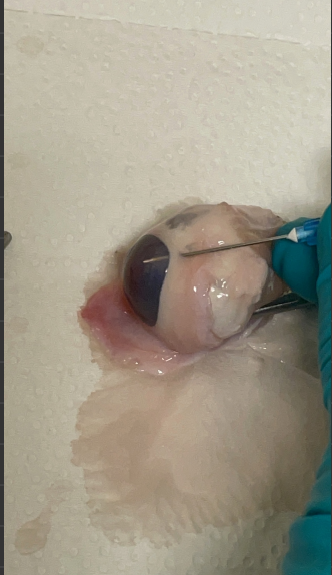

Before I went to capstone on Wednesday, Kierstin, Dr. Rickard and I did a demonstration where we inflated and deflated an eye with the pressure from a water column when raised. This helped we gain better understanding of the eye in general and what increased pressure in the eye actually looks like.       In class time we performed multiple eye surgeries. The main goal for this testing was to ge the inlet tube into the eye. The eye was poked with a needle, and the small tubing was inserted, but this proved to be very difficult because of the flexibility in the tube as well as the small size. Dr. Rickard gave us some tips including have the tube cut on a slant to create more of a point for the insertion. He also sad to spin the needle around to create a slightly larger hole than necessary. With his advice we were able to get it. We then disposed of the eyes into the dumpster.  The rest of my time was spent on the poster. In the coming we...

Lab time with Brinkley:  Brinkley and I did simulations where we had a water column at an unhealthy eye level (Clamped to a retort stand at the top) and created a system with tubing that connected the water column to a pig eye. We used a needle and placed it inside the anterior chamber. When we moved the water column up and down we observed the eye pressure physically increase and decrease. This was helpful to understand where we needed to insert the tubing for the surgery simulation, and also observe healthy and unhealthy eye pressure.  In Class:  Lab time with Brinkley and Alex:  Pig eye surgery simulation:  This week during our lab time surgery simulation we focused more on surgically implanting the tube into the anterior chamber, rather than making a pocket and implanting an actual valve. This part was really important to learn how to do because without it we can’t see how our valve would actually work because we wouldn’t be able to get any flow....